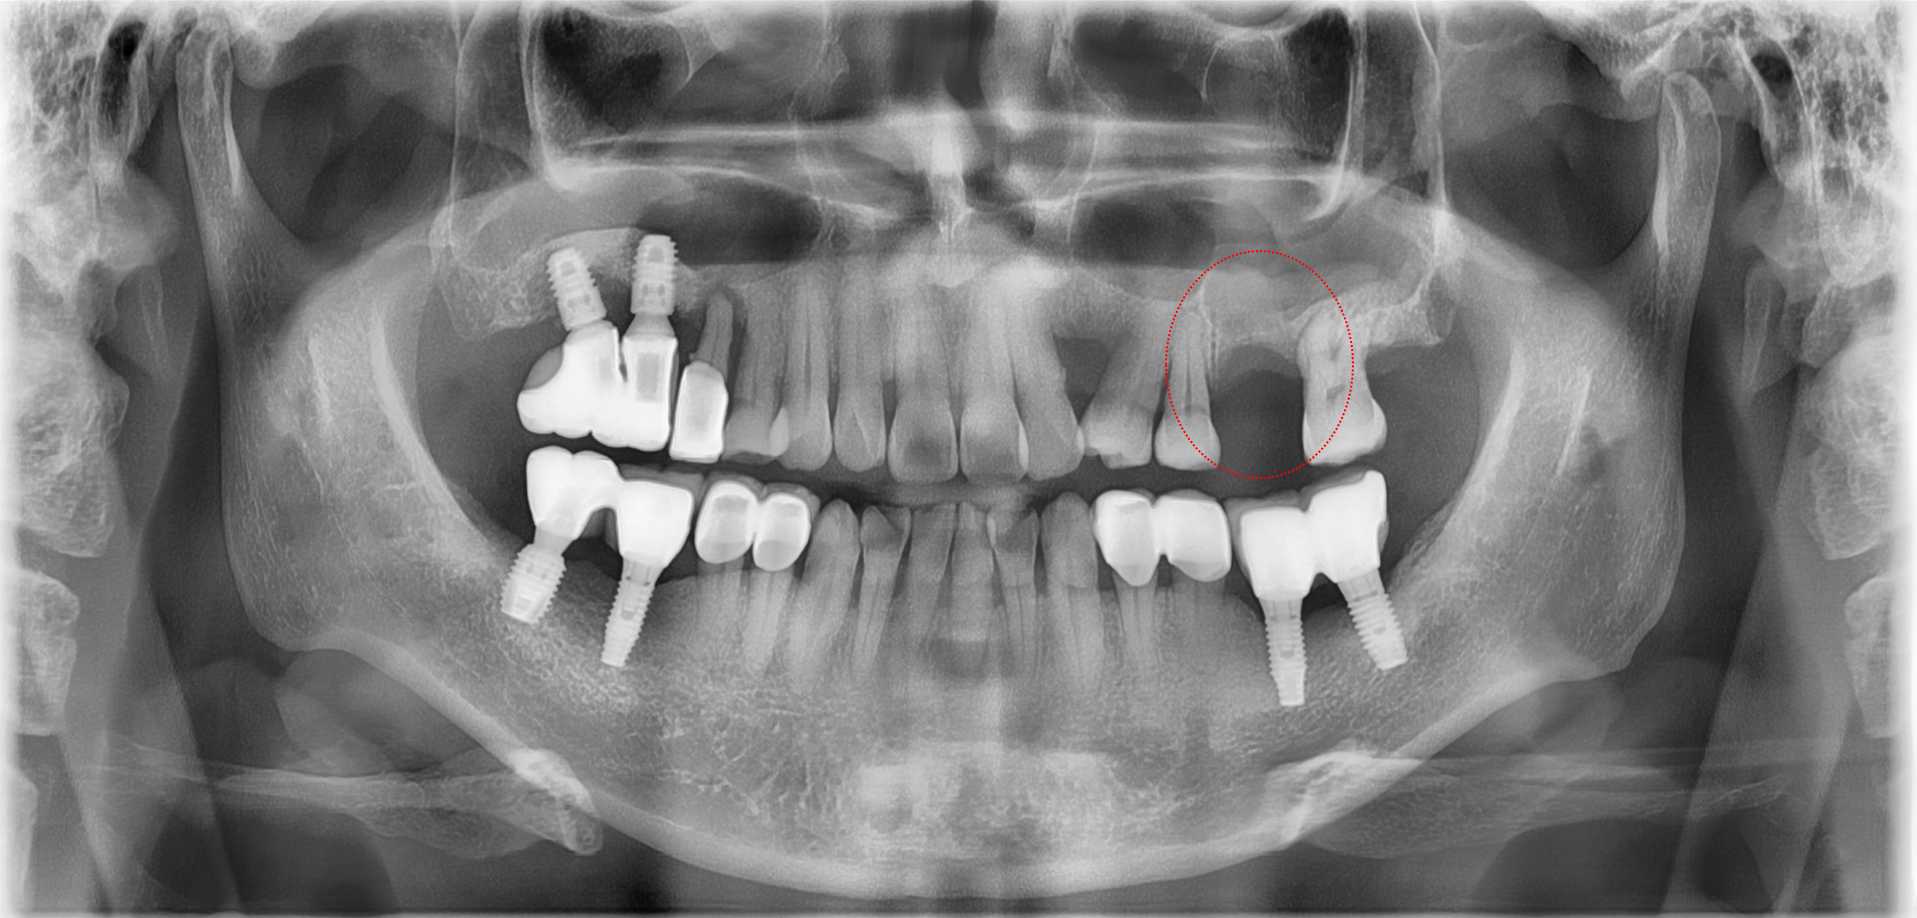

<치료 전>

왼쪽 어금니 부위(사진상 오른 쪽)의 파노라마 엑스레이를 보면 상악동 때문에 잇몸뼈가 거의 없습니다.

임플란트를 심기위해서는 상악동 골이식이 필요합니다.

<치료 후>

붉은 점선 부위가 상악동 골이식으로 새롭게 뼈가 생생된 부분입니다.